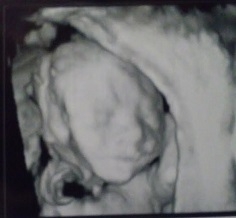

All the 3D ultrasounds I've gotten in the past were FREAKY looking and not at all what I wanted to see- until I got this one and the new guy basically looks like his sleeping big brother! (watermark to discourage baby-photo stealing)